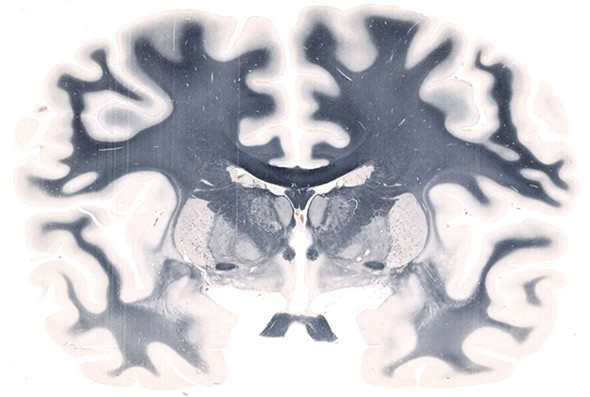

Whole Mount Brain - 5

Whole Mount Brain - 5" x 7" at 20X. Image credit: Huron Digital Pathology.